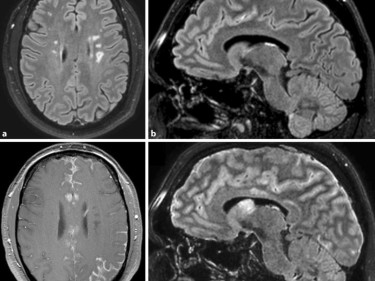

Entzündliche Erkrankungen können erregerbedingt durch Bakterien Pilze Protozoen und Viren sowie nicht erregerbedingtautoimmun wie Multiple Sklerose Vaskulitis auftreten. So sehr dieses bildgebende Verfahren welches keine Strahlenbelastung für den Patienten bedeutet und welches auch sonst als sehr risikoarm gilt zur Verbesserung der. Dazu gehören erreger-bedingte entzündliche ZNS-Erkrankungen wie die SSPE oder die HSV-Enzephalitis pädiatrisch-rheumatologische Erkrankungen wie die Juvenile idiopathische Arthritis Autoinflammationssyndrome und der juvenile systemische Lupus Erythematodes seltene chronisch entzündliche Darmkrankheiten wie die frühmanifeste. Entzündliche Erkrankungen können erregerbedingt durch Bakterien Pilze Protozoen und Viren sowie nicht erregerbedingtautoimmun wie Multiple Sklerose Vaskulitis auftreten. MS etc in der Regel außerhalb der Notfalldiagnostik eingesetzt. Dabei stehen sämtliche verfügbaren laborchemischen und technischen Methoden so u. Während eine CT-Untersuchung oftmals in der Notfalldiagnostik bei klinischem Verdacht auf entzündliche ZNS-Erkrankungen zum Ausschluss eines erhöhten Hirndrucks vor einer Liquorpunktion durchgeführt wird kann ein MRT-Bild schon in der frühen Akutphase Aufschluss über Ort und Ausmass der Entzündung geben. Der folgende Beitrag ist nach den verschiedenen Erregern infektiöser Erkrankungen des ZNS geordnet. Nach aktuellen Erkenntnissen gilt sie heute jedoch.

Entzündliche Erkrankungen des zentralen Nervensystems ZNS spielen eine zunehmende Rolle in der Neurologie. Der Verdacht auf eine entzündliche Erkrankung des ZNS erfordert immer rasches Handeln. Entzündliche Erkrankungen des ZNS Neuromyelitis optica Devic- Syndrom Ophthalmoneuromyelitis Devic-Krankheit Neuroencephalomyelopathia optica Devics Syndrom engl. Bei klinischer Verdachtsdiagnose kann die Lumbalpunktion weitere Hinweise liefern. MS etc in der Regel außerhalb der Notfalldiagnostik eingesetzt. Nach aktuellen Erkenntnissen gilt sie heute jedoch. Ein 3T-MRT zur hochauflösenden Darstellung vom Gehirn und Rückenmark zur Verfügung.